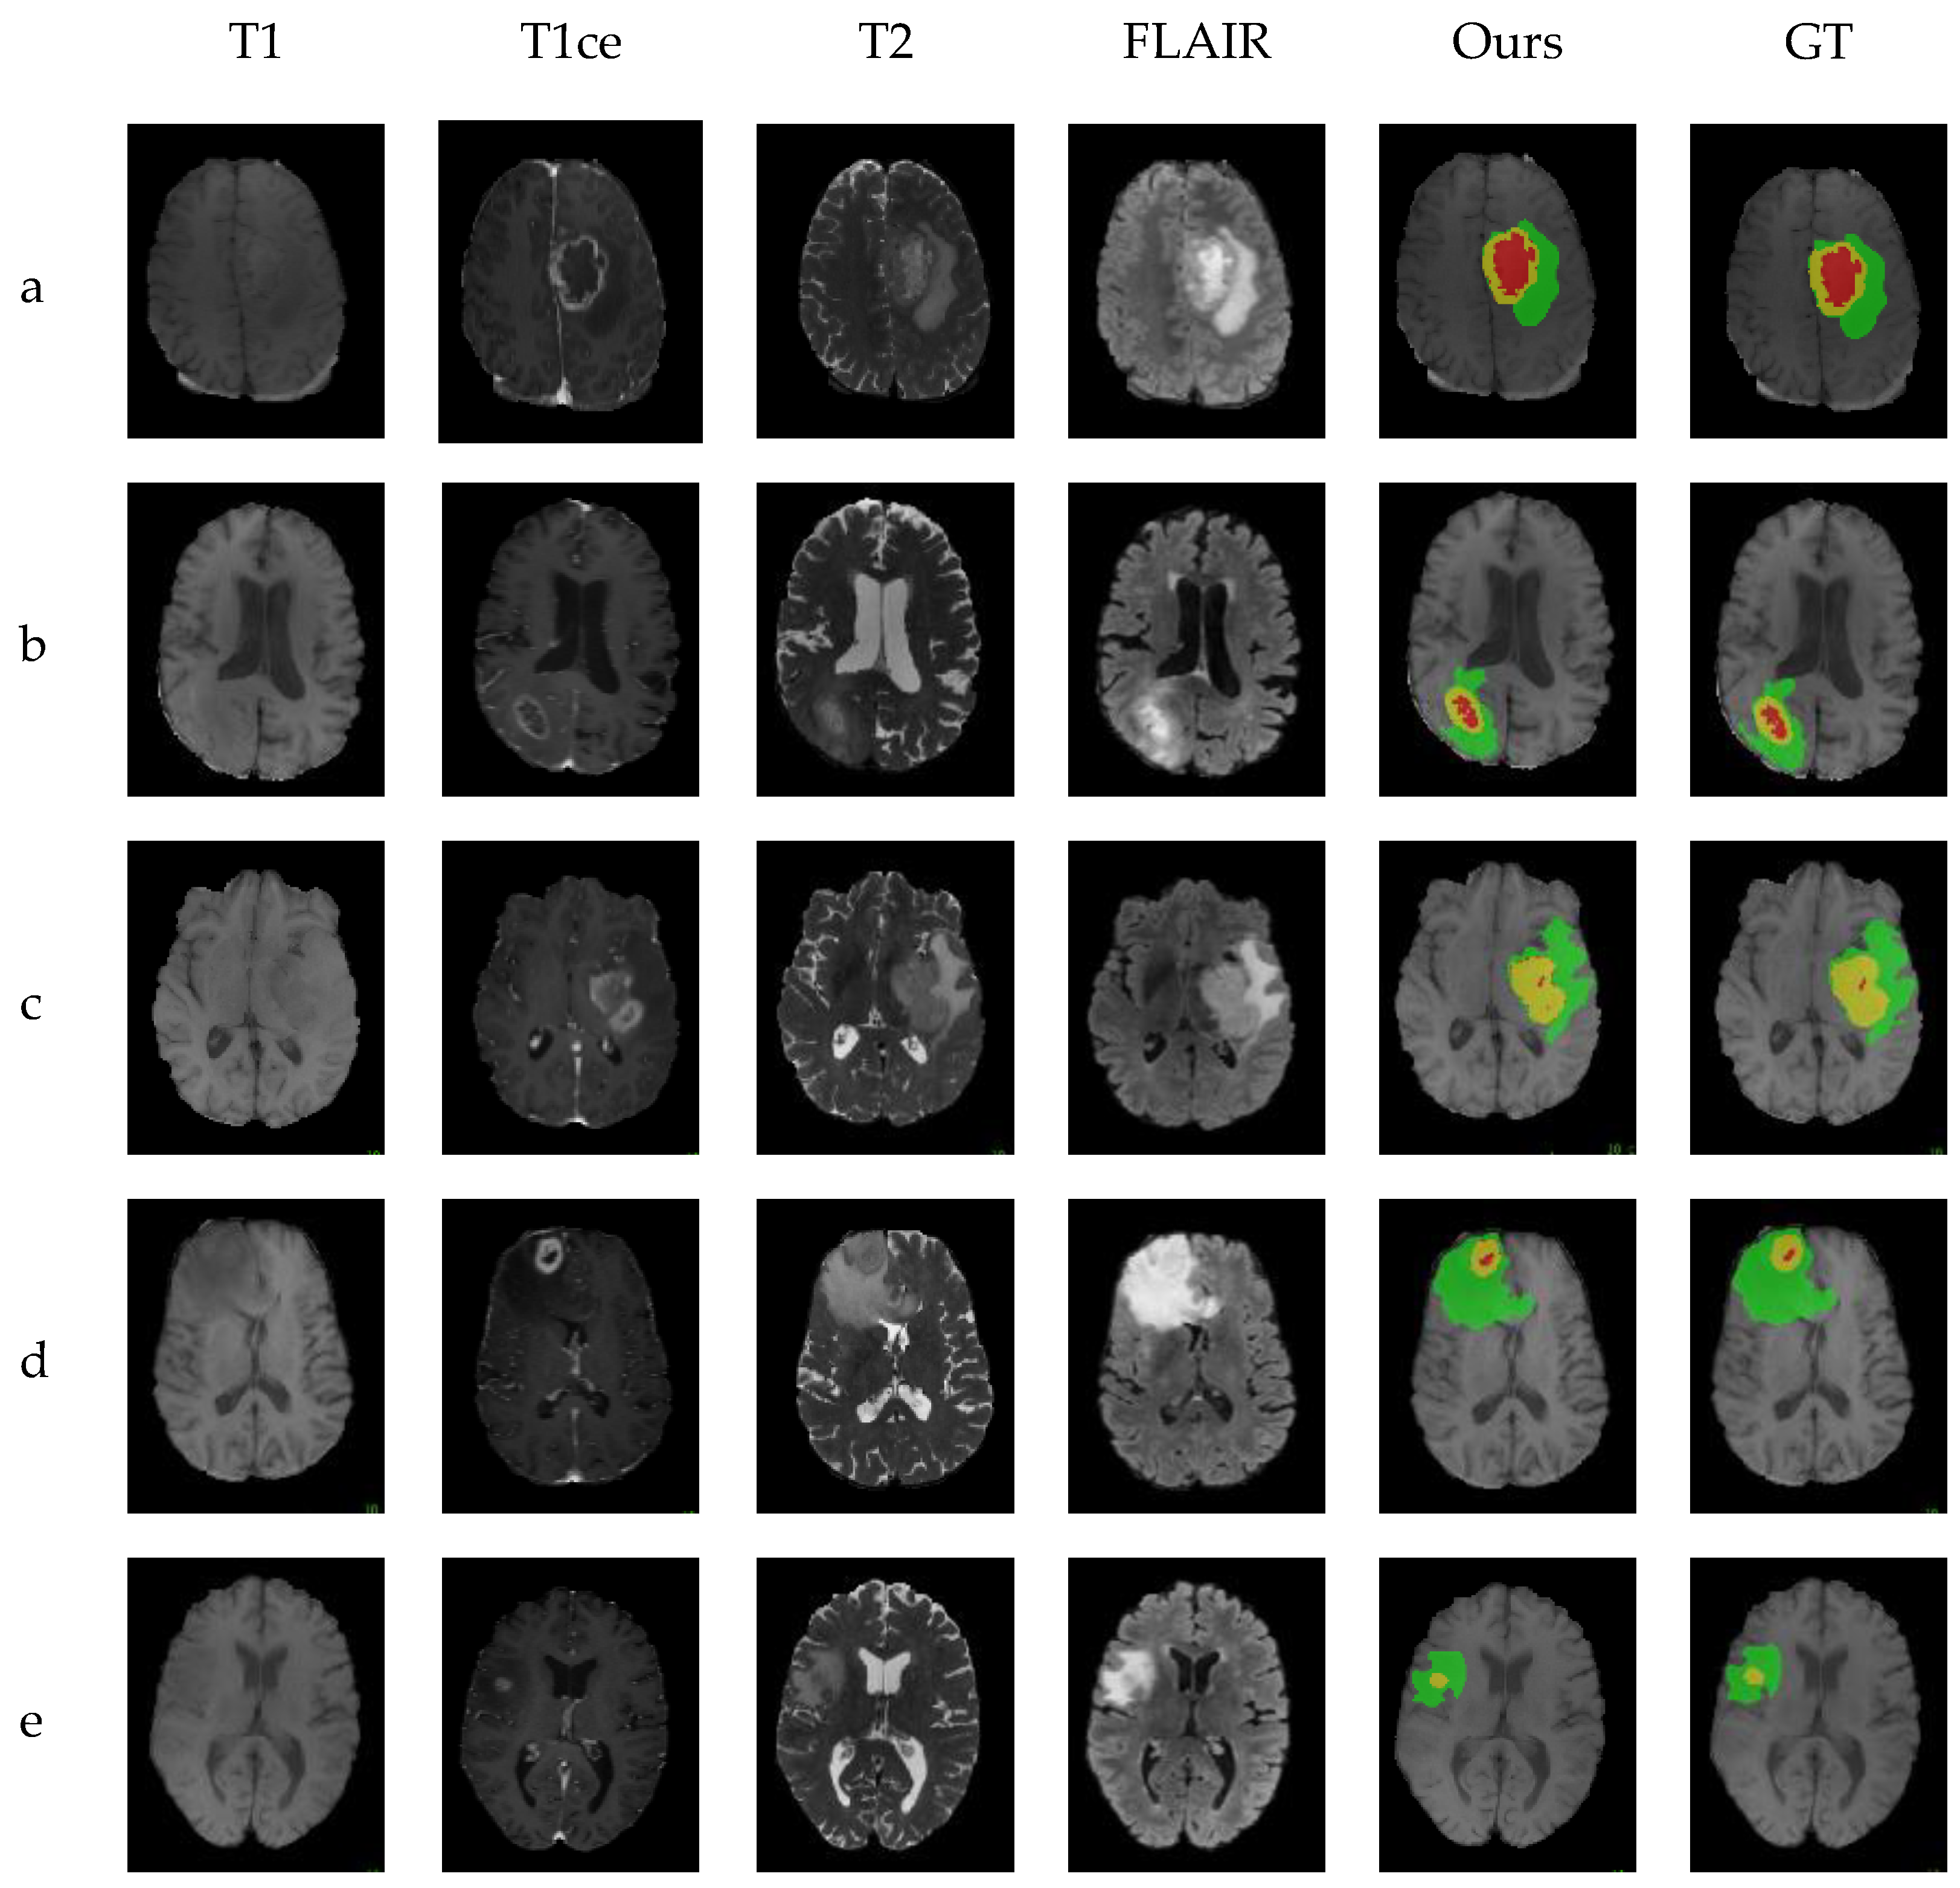

Figure 7 shows the visualization results of the SARFNet model on the BraTS2021 [69] dataset, from which five cases are randomly chosen. The medical case numbers 003_107, 020_84, 56_76, 62_83, and 66_80, according to sequences a, b, c, d, and e, are segmented by the SARFNet. Green, yellow, and red represent the whole tumor, tumor core, and enhancing tumor, respectively. The results of SARFNet are close to the labeled ground truth. Compared with the variant network based on UNet, the best MBANet has lower indicators. We also overcame the networks based on Transformer. In general, our architecture and modules achieved excellent results on BraTS2018, which can provide a good basis for subsequent research.

Figure 7.

Visualization results of medical cases. From left to right: T1, T1ce, T2, FLAIR, the result segmented by SARFNet, and the ground truth. Green, yellow, and red represent the whole tumor, tumor core, and enhancing tumor, respectively.